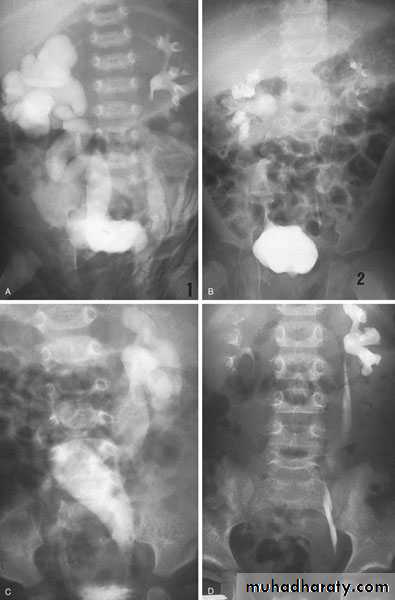

Diagnosis:

IVU, cystoscopy, cystogram

The ‘adder head’ on excretory urography is typical.

Cobra (Adder) head appearance of ureterocele

Congenital  anomalies of the upper urinary tract

Ureterocele involving single system Ureterocele involving duplicated ureter